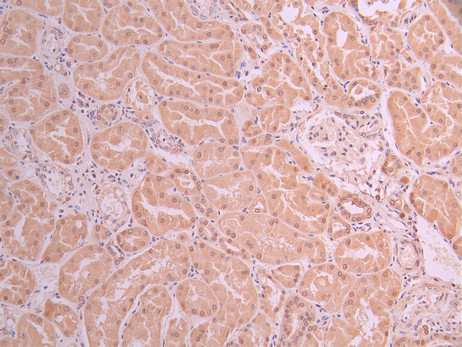

IHC image of CSB-RA948463A0HU diluted at 1:100 and staining in paraffin-embedded human kidney tissue performed on a Leica BondTM system. After dewaxing and hydration, antigen retrieval was mediated by high pressure in a citrate buffer (pH 6.0). Section was blocked with 10% normal goat serum 30min at RT. Then primary antibody (1% BSA) was incubated at 4°C overnight. The primary is detected by a Goat anti-rabbit polymer IgG labeled by HRP and visualized using 0.05% DAB.